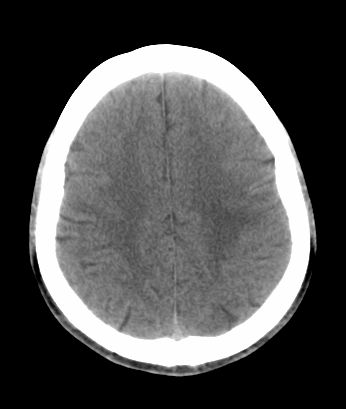

男 42岁 头痛20天

左顶叶见片状低密度影,边界不清,内见斑片状等密度影。考虑转移性肿瘤可能性大,建议ct增强或mr增强扫描。建议胸部检查,排除肺部病变。

左顶叶见片状低密度影,内似见结节状略高密度影,建议增强扫描。

左侧顶叶低密度灶,性质待定;建议行ct增强扫描或mri检查。

左顶叶见片状低密度影,边界不清,内见斑片状等密度影。考虑转移性肿瘤可能性大,建议ct增强或mr增强扫描。建议胸部检查,排除肺部周围型腺癌。